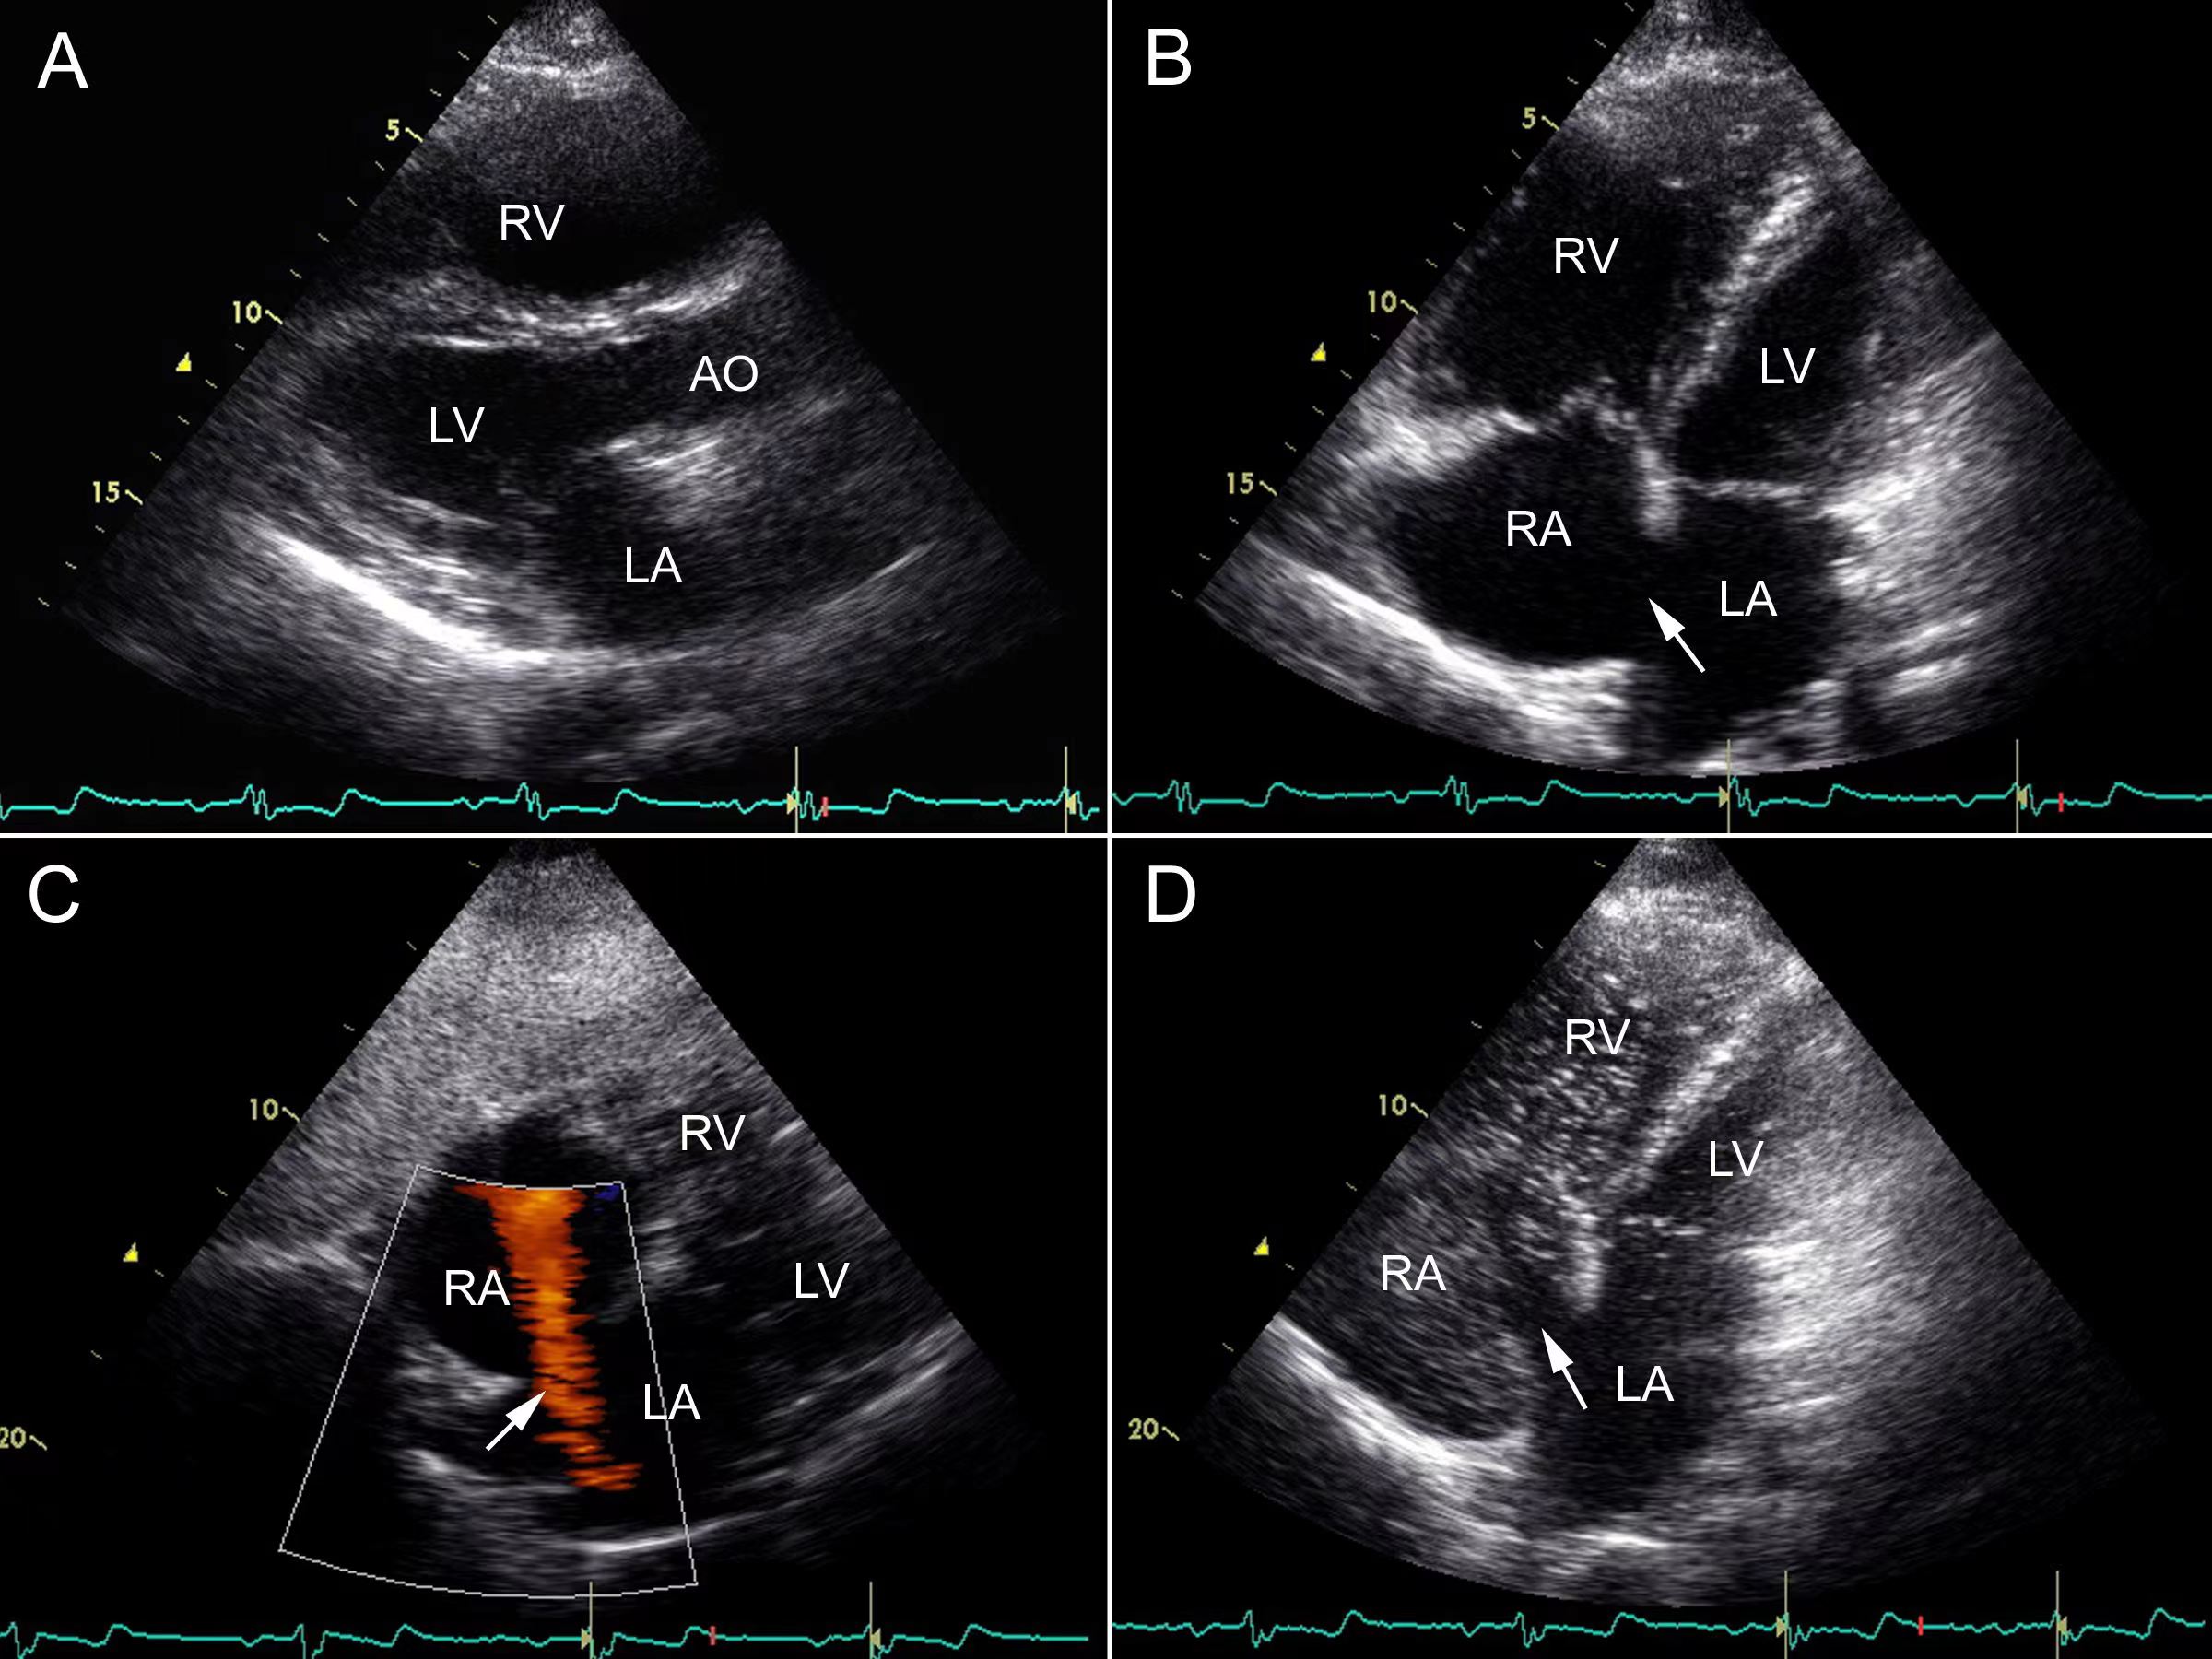

在这里我们来科普一下吧,房间隔缺损是最常见的先天性心脏病之一,简单来说,正常人的心脏分四个腔,分别是左心房,右心房,左心室,右心室,在左、右心房之间,有一个间隔,叫做房间隔,它将左、右心房分隔开来,互不相通。如果胚胎发育过程中出了问题,导致左右心房之间留有空隙(缺损),这就叫做房间隔缺损。房间隔缺损分为原发孔型、继发孔型、静脉窦型及冠状静脉窦型。其中,继发孔型主要指中央型,静脉窦型包含下腔型及上腔型。兼有上述两种以上者,称为混合型。

如何发现房间隔缺损呢?房间隔缺损儿童时期一般无症状,随年龄增长症状逐渐显现,劳力性呼吸困难为主要表现。一些小的房间隔缺损不会引起任何症状,往往在体检的时候或者就诊医生听诊的时候,发现心脏杂音。心脏彩超检查是目前最简单有效的检查手段,可以发现房间隔缺损的类型、位置以及大小。

房间隔缺损怎么治疗呢?现在的治疗方法包括两种,一种是微创手术介入治疗,通常叫房间隔封堵术,是通过静脉穿刺,用一个封堵器,把缺损的洞堵起来,但是要求房间隔缺损的周围有足够长的残端,能够支撑这个封堵器,目前房间隔缺损的封堵,只要有适应症,治疗效果很好,可免开胸之苦。如果不能做介入治疗,则需要选择开胸治疗,打开将缺损的地方补上,效果也很好,介入治疗和外科手术治疗都是根治性手术。如果没有及时接受治疗,随着疾病的发展,可能会导致肺动脉高压,心力衰竭等并发症,缩短患者寿命,降低生活质量。如果及时接受正规治疗,一般效果良好,患者的生活质量明显提高。